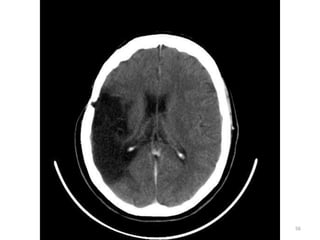

• Da região da cabeça, a área mais estuda é o

REVISÃO ANATÔMICA

vasculares, tumorais, deformidades e do

sistema nervoso central.

• Trata-se de uma região com grande riqueza

anatômica, necessitaríamos de muito tempo

para discutir todas. Vamos elencar as mais

importantes no desenvolvimento do exame.